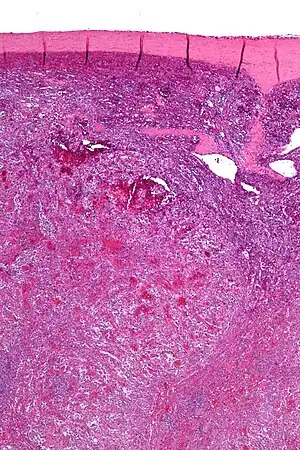

| Low magnification micrograph of a littoral cell angioma. H&E stain. | |

Littoral cell angioma, abbreviated LCA, and formally known as littoral cell angioma of the spleen, is a benign tumour of the spleen that arises from the cells that line the red pulp.[1]

Littoral cell angiomas show in CT scans. They are diagnosed by pathologists by taking a sample of the tumour via Fine Needle Aspiration or Core Needle Aspiration or from a splenectomy. Histologically, they have anastoming small vascular channels and cystic spaces with papillary projections.[2]